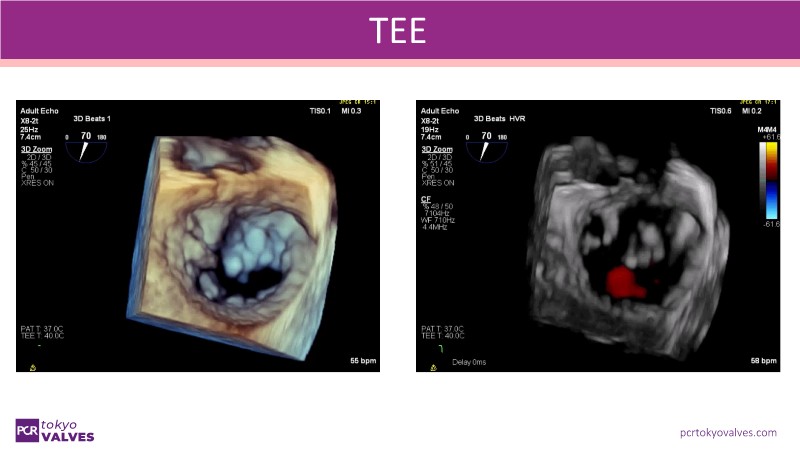

Explore the latest advancements in TEER therapy with this PCR Tokyo Valves 2025 session dedicated to MitraClip. Through expert-led case discussions, gain a deeper understanding of complex scenarios, including restricted posterior leaflet in functional mitral regurgitation, commissure lesion (A3P3), and MitraClip combined with Amulet.

- To learn about atrioventricular valve morphology and the associated treatment challenges with TEER